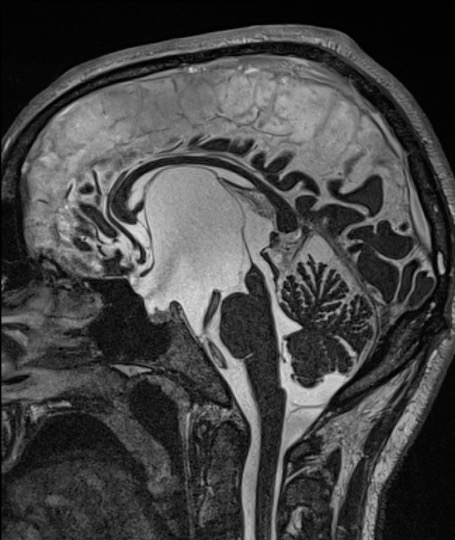

le kyste est développé dans un dédoublement de la membrane Liliequist, il soulève le plancher du V3 et se développe dans le 3ème ventricule, voire les ventricules latéraux.

c’est le meilleur exemple de kyste arachnoïdien avec mécanisme de clapet arachnoïdien qui trappe le LCS dans le kyste ; on le constate de visu lors de l’intervention endoscopique.

il entraîne donc une hydrocéphalie en principe obstructive ; en fait, il peut s’associer à une part d’hydrocéphalie dite communicante, et un certain nombre de patients ne sont donc pas guéris avec le seul traitement du kyste, ils nécessitent alors la pose d’une valve dans les suites.

elle est réalisée chaque fois que possible. le plus souvent il existe une dilatation ventriculaire qui donne accès au kyste. la fenestation endoscopique permet d’ouvrir le dôme du kyste, d’y pénétrer et d’ouvrir le fond du kyste dans les citernes de la base. Il s’agit donc d’une ventriculo-kysto-cisternostomie.

en post-opératoire, les ventricules restent dilatés, en général non sous pression

on objective la perméabilité des membranes du kyste et du plancher du 3ème ventricule. dans certains cas, une hydrocéphalie communicante peut se révéler secondairement.